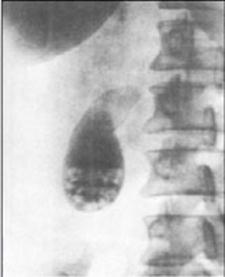

Холецистограмма (камни на дне желчного пузыря)

Пероральная холецистография представляет собой рентгенологическое исследование желчного пузыря после приема контрастного препарата. Показанием к пероральной холецистографии являются симптомы нарушения проходимости желчных путей (боль в правом подреберье, непереносимость жиров, желтуха). Исследование, как правило, проводят для подтверждения диагноза при заболеваниях желчного пузыря. После приема рентгеноконтрастного вещества оно всасывается в тонкой кишке, поступает в печень, откуда попадает в желчь и накапливается в желчном пузыре. Его наибольшее наполнение обычно достигается спустя 12-14 ч после приема, в это время выполняются снимки пузыря с целью выявления особенностей его конфигурации.

Дополнительные данные можно получить после назначения жирной пищи, способствующей сокращению и опорожнению желчного пузыря, при этом желчь поступает в общий желчный проток и тонкую кишку. Снимки, выполненные в это время, позволяют оценить эвакуаторную функцию желчного пузыря и проходимость общего желчного протока.